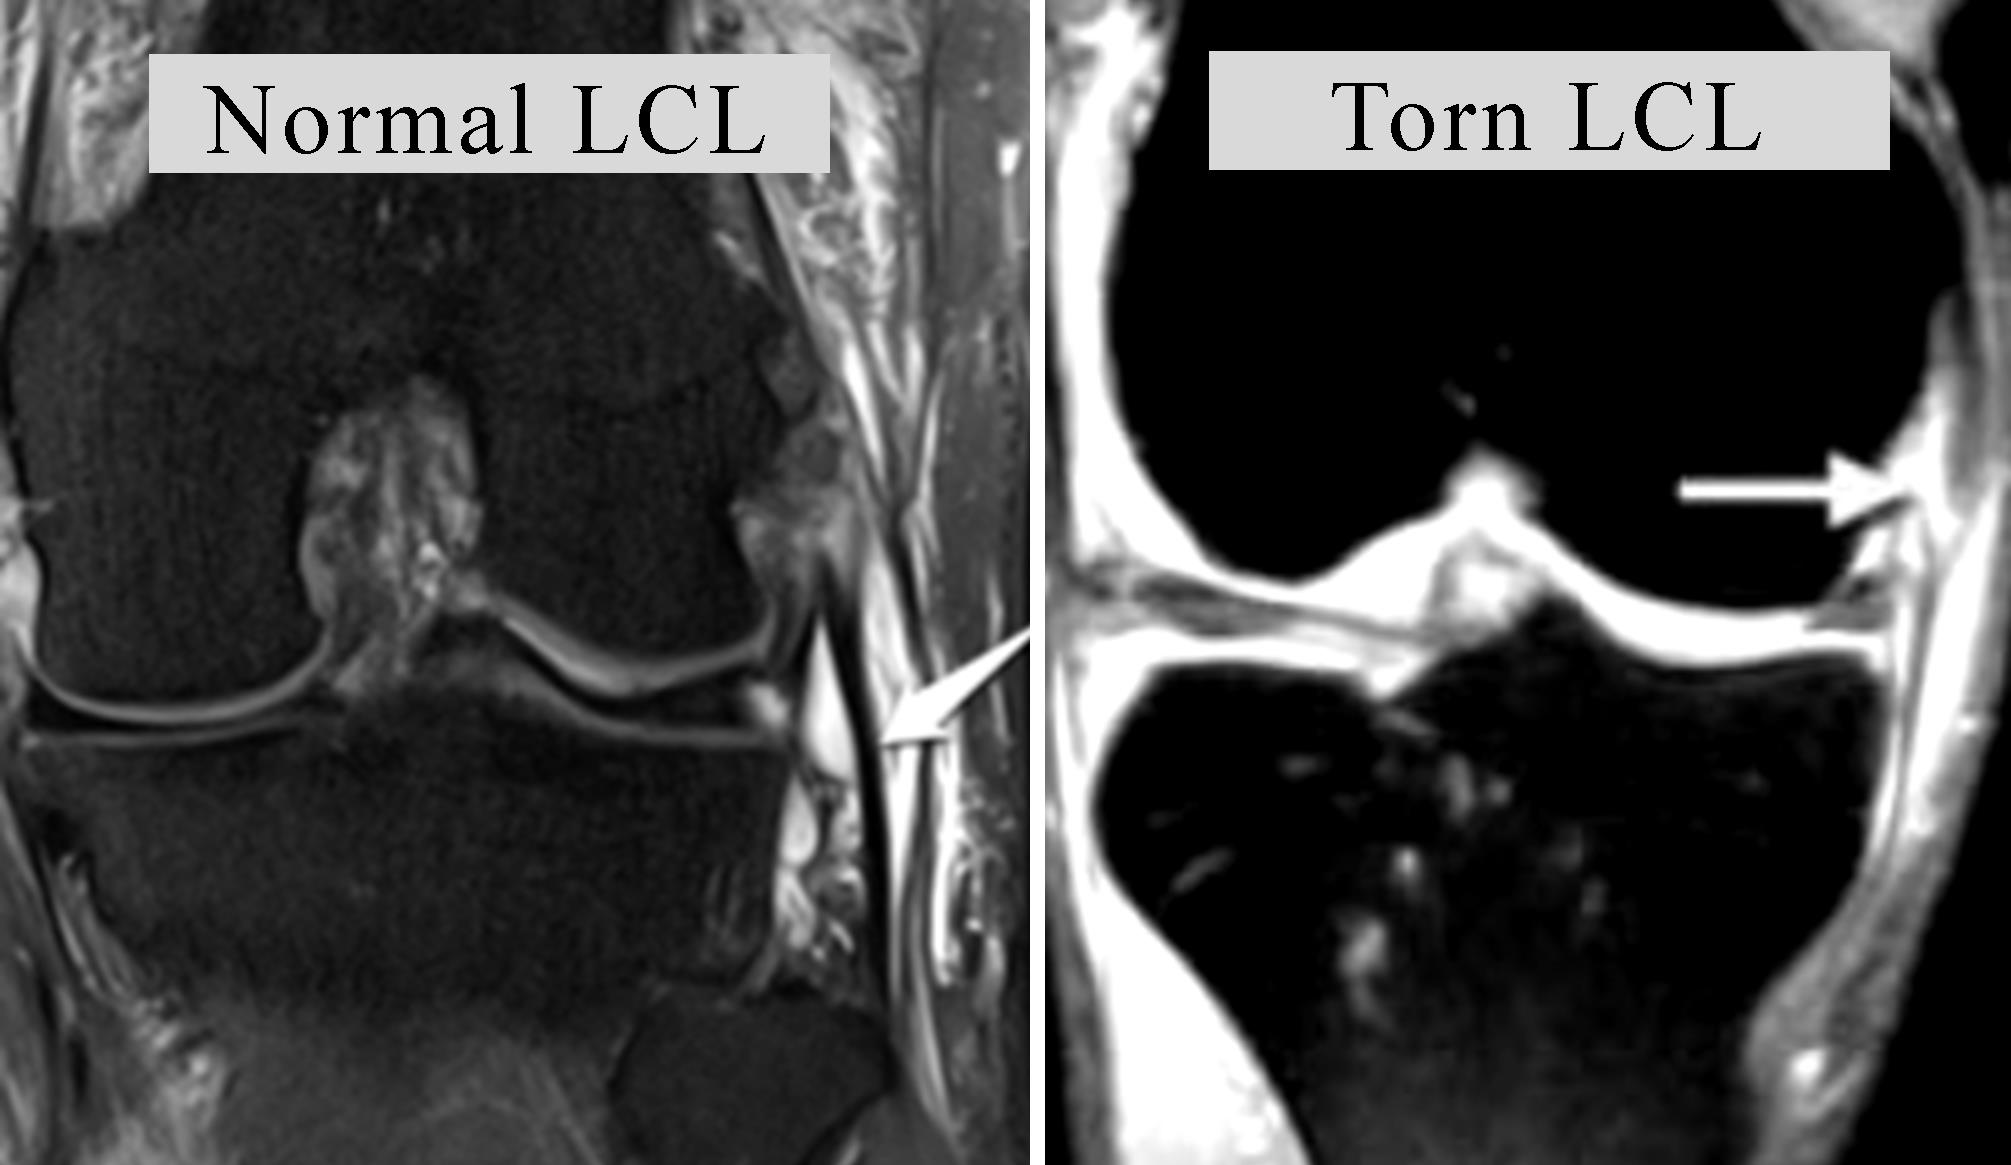

- MRI scans: This displays images of soft tissues in the knee, including the LCL. MRI scanning is more than 90 percent accurate in evaluating LCL injury severity.